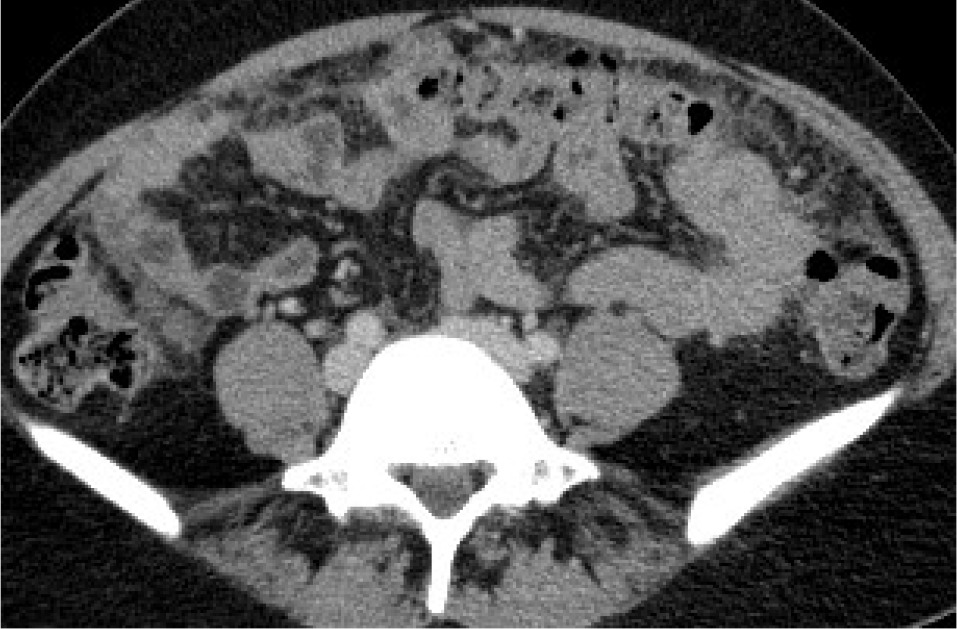

Figure 1

Female, 61-year-old. Serous ovarian cancer. A) Computed tomo graphy (CT) – small implant in the left paracolic gutter. B) CT – thickened pelvic peritoneum in the pouch of Douglas. C) Axial T2WI. D) DWI (b = 800 s/mm2)